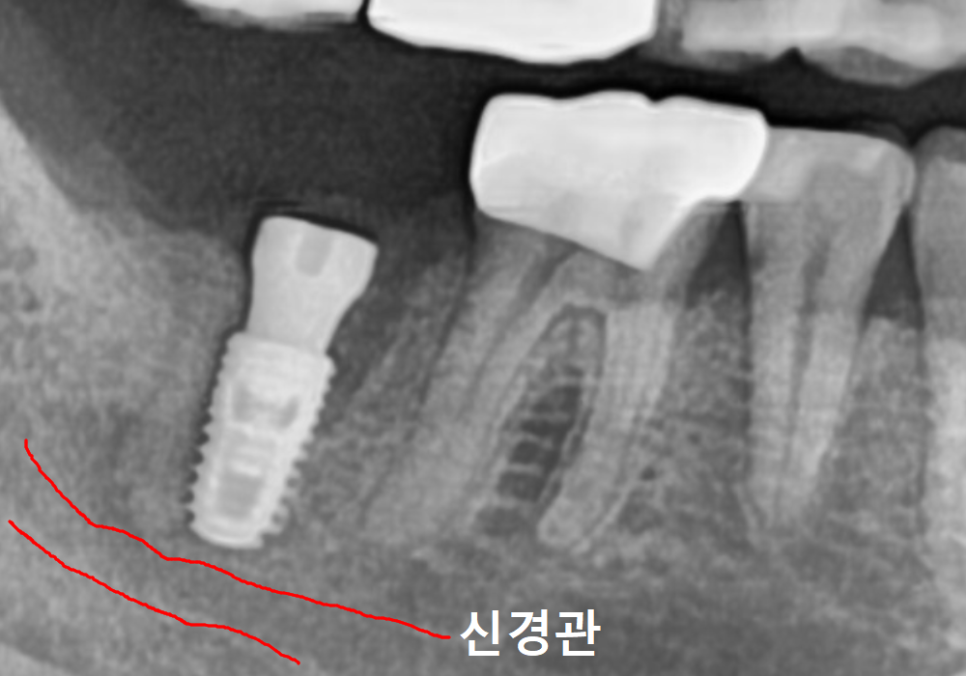

3D CT를 볼까요?

빨갛게 표시한 부분은

아래턱의 감각을 담당하는 주요 신경인

하치조 신경이고,

노란색 부위가 염증으로 인해

뼈가 녹아버린 공간이에요.

임플란트를 심을 때 가장 중요한 것은

이 신경을 피해 안정적으로 식립하는 것인데요.

이 상태에서 바로 심게 되면

뼈가 녹아 텅 빈 공간에 임플란트 뿌리가

제대로 고정될 수 없겠죠~

또한 임플란트가 지지력을 얻으려면

최소 7~8mm의 뼈 길이가 확보되어야 하는데,,

사진을 보면 뼈가 녹은 지점부터

신경까지의 거리가 거의 닿을 듯 가깝습니다.

이런 경우 무리하게 바로 심다가는

자칫 신경을 건드릴 위험이 커요.

그래서 이런 케이스의 경우,

뼈가 먼저 튼튼하게 회복하기를 기다려준 뒤,

뼈가 안정적으로 생성이 되면

임플란트를 식립해야 합니다.

염증을 제거하고 뼈이식을 진행한 뒤,

뼈가 튼튼하게 굳기를 2개월 정도 기다렸습니다.

잇몸뼈가 안정적으로

생성된 것을 확인한 뒤,

하치조 신경을 피해 안전하게

잘 식립된 모습입니다.